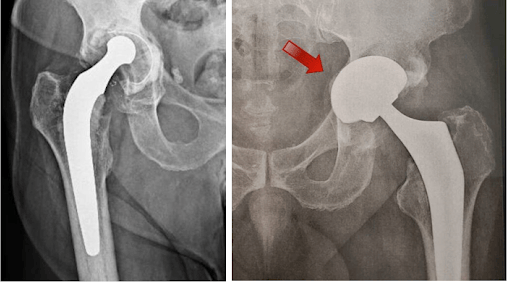

Radiografias mostrando solturas da prótese de quadril.

A soltura é confirmada com a realização de radiografias ou outros exames de imagem como tomografia, ressonância ou cintilografia.

Caso se confirme a soltura (também chamada de afrouxamento) da prótese, necessitamos fazer outra cirurgia, chamada de revisão de prótese, para retirada do componente solto e colocação de novo componente, geralmente de maior tamanho que o antigo, para garantir melhor fixação ao osso.